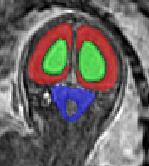

Limiting failures of machine learning systems is of paramount importance for safety-critical applications. In order to improve the robustness of machine learning systems, Distributionally Robust Optimization (DRO) has been proposed as a generalization of Empirical Risk Minimization (ERM). However, its use in deep learning has been severely restricted due to the relative inefficiency of the optimizers available for DRO in comparison to the wide-spread variants of Stochastic Gradient Descent (SGD) optimizers for ERM. We propose SGD with hardness weighted sampling, a principled and efficient optimization method for DRO in machine learning that is particularly suited in the context of deep learning. Similar to a hard example mining strategy in practice, the proposed algorithm is straightforward to implement and computationally as efficient as SGD-based optimizers used for deep learning, requiring minimal overhead computation. In contrast to typical ad hoc hard mining approaches, we prove the convergence of our DRO algorithm for over-parameterized deep learning networks with ReLU activation and a finite number of layers and parameters. Our experiments on fetal brain 3D MRI segmentation and brain tumor segmentation in MRI demonstrate the feasibility and the usefulness of our approach. Using our hardness weighted sampling for training a state-of-the-art deep learning pipeline leads to improved robustness to anatomical variabilities in automatic fetal brain 3D MRI segmentation using deep learning and to improved robustness to the image protocol variations in brain tumor segmentation. Our code is available at https://github.com/LucasFidon/HardnessWeightedSampler.